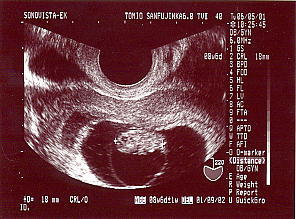

9週目の切迫流産のエコー 赤ちゃんは下向きで頭が左です。 赤ちゃんが包まれてる黒っぽい所の左 薄い縦長の陰が出血です。 18ミリです。 |